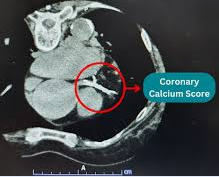

Hastaların çalışmanın başında ve sonunda eşlendirilmiş Photon-Counting CT (PCCT) ile toplam plâk hacmi ve plak bileşenleri (özellikle kalsifiye plak) nicel olarak ölçüldü.

▶ Toplam plak hacmi 12 ayda 417 mm³ → 498 mm³’e yükseldi.

▶ Kalsifiye plak miktarı %28 arttı: 214 mm³ → 275 mm³.

PCCT nedir?

PCCT X ışınlarını ışığa dönüştürüp sinyali ortalamak yerine, tek tek fotonları sayıyor ve enerjilerini ölçüyor ve daha yüksek uzaysal çözünürlükle kalsiyumu gerçek sınırlarında gösteriyor.

Plâk hacmini ve bileşenlerini nesnel ve hassas şekilde ölçüyor.

Zaman içinde plak değişimini takip etmeyi mümkün kılıyor.

Geleneksel koroner BT anjiyografide (CCTA) kalsiyum “blooming” artefaktı yaratır ve stenozu abartır.